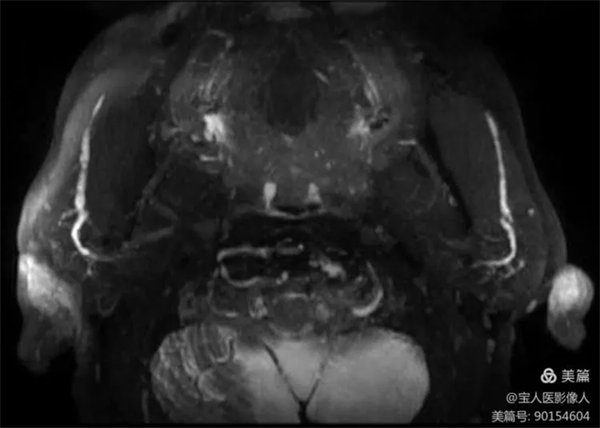

患者磁共振檢查,可清晰地顯示正常腮腺導管主干和大分支導管。

圖3,雙側腮腺導管主干及分支軸位圖像

醫學影像科副主任張軍暉醫生介紹,此圖像是在常規檢查中重建顯示腮腺導管主干及部分分支。如果行專門的腮腺導管磁共振成像技術,通過一些前期準備及掃描技術優化,成像效果會更好,結合強大的后處理技術,會更好的顯示腮腺導管及周圍組織結構。

2、腮腺導管MR成像,為無創性檢查,無需造影劑,避免了X線造影可能因造影劑產生的不良反應及導管破裂及感染的風險,更加安全,已逐步替代腮腺X線造影檢查。

觀察腮腺及其導管有無病變,病變的性質和范圍。常用于腮腺腫瘤、慢性腮腺炎等疾病的診斷,也可用于干燥綜合征的輔助診斷。